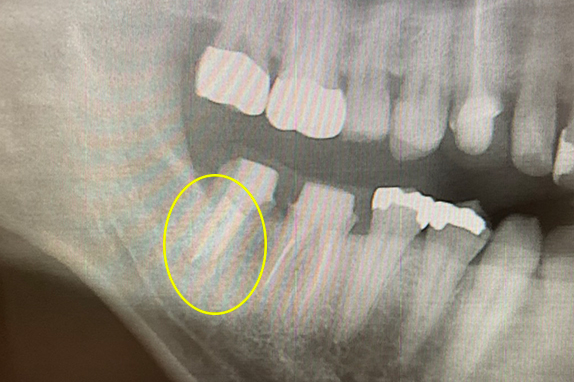

CASE 07 マイクロエンド(精密根管治療)+歯根周囲掻爬(歯周外科)

-

- 主訴

- 歯ぐきがよく腫れる(10代女性)

-

- 回数期間

- 7回 約1年半

-

- 治療法

- マイクロエンド(精密根管治療)、歯根周囲掻爬(歯周外科)

-

- 治療費用

- 約35万円(税抜)

歯ぐきがよく腫れる主訴で来院。レントゲン写真の術前を見ると大きな影が確認できます。この部分に嚢胞(のうほう)がある状態です。マイクロエンドと歯根周囲掻爬(歯周外科)をすることで改善したケースです。

<リスク・副作用>

治療後は痛み、腫れ、痺れなどの副作用が生じる場合があります。症状が再発する可能性があります。